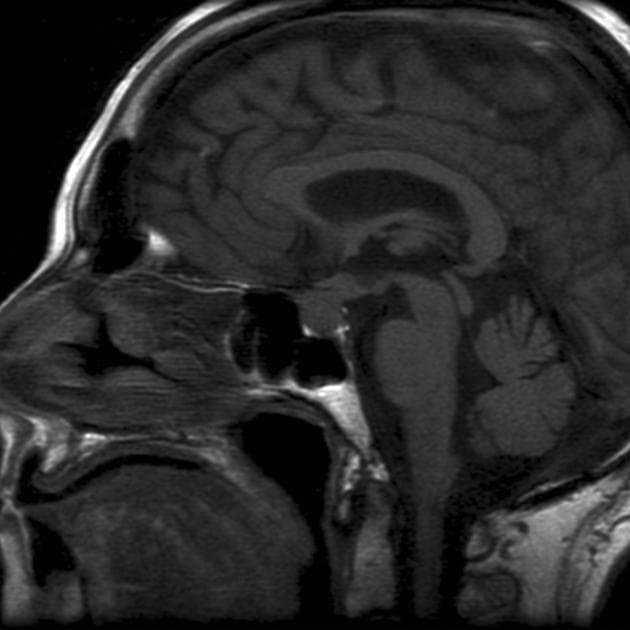

Sagittal T1

MRI•Sagittal T1•1 Img

- Khối liên tục với cuống yên, làm giãn cuống này cả phía trên và phía dưới.

- Phù hợp với kiểu tăng quang đặc trưng và nằm trong cuống yên (infundibulum).

- Khối phù hợp với kiểu tăng quang đặc trưng và nằm trong cuống yên (infundibulum).

- Khối liên tục với cuống yên, làm giãn cuống cả phía trên và phía dưới.

- "Đặc điểm hình ảnh gồm khối u ranh giới rõ, tăng quang mạnh, liên tục với và làm giãn cuống yên."

U Pituicytoma là một loại khối u thần kinh đệm lành tính, phát triển chậm và hiếm gặp, xuất phát từ các tế bào pituicyte ở thùy sau tuyến yên hoặc cuống yên. Khối u thường biểu hiện như một tổn thương ranh giới rõ, tăng quang mạnh và liên tục với, đồng thời làm giãn cuống yên. Trên cộng hưởng từ (MRI), khối u thường có tín hiệu đẳng trên hình ảnh T1 và tăng quang đồng nhất sau khi tiêm thuốc cản quang. Việc không có dấu hiệu ác tính, không bệnh toàn thân và tổn thương ổn định dài hạn trên hình ảnh học làm tăng khả năng chẩn đoán u Pituicytoma, ngay cả khi chưa xác định bằng mô bệnh học. Các chẩn đoán phân biệt bao gồm u tuyến yên có liên quan đến cuống yên, u màng não và bệnh tổ chức bào Langerhans, những bệnh này có thể có hình ảnh tương tự. Tuy nhiên, vị trí đặc hiệu trong cuống yên và sự liên tục với cuống làm nghiêng về chẩn đoán u Pituicytoma. Điều trị thường mang tính theo dõi bảo tồn, đặc biệt ở bệnh nhân không có triệu chứng.